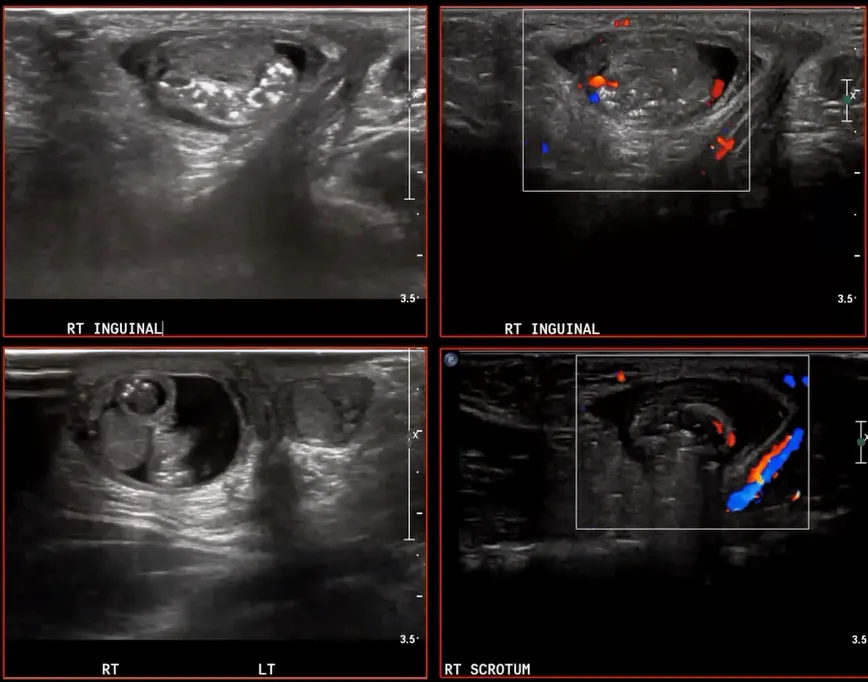

incarcerated hernia. 도플러에서 아직 flow가 보여서, stranglation은 아직인 듯

reactive hydrocele 이 관찰됨.